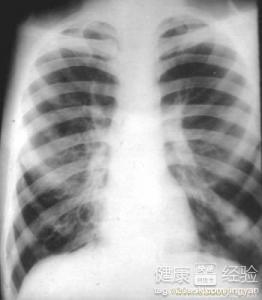

支氣管炎是一種常見的呼吸系統(tǒng)疾病,其癥狀包括咳嗽、咳痰、呼吸急促等,許多患者關(guān)心的問題是:支氣管炎能自愈嗎?本文將詳細(xì)解析支氣管炎的類型、癥狀、治療方法以及能否自愈的問題,幫助患者更好地了解并應(yīng)對這一疾病。

支氣管炎是指氣管、支氣管黏膜及其周圍組織的炎癥,根據(jù)其發(fā)病的急緩,可分為急性支氣管炎和慢性支氣管炎,急性支氣管炎通常由于病毒、細(xì)菌等感染引起,癥狀明顯且病程較短;而慢性支氣管炎則由于長期吸煙、空氣污染等因素導(dǎo)致,癥狀持續(xù)較長時間,易反復(fù)發(fā)作。

支氣管炎的典型癥狀包括咳嗽、咳痰、呼吸急促等,部分患者可能伴有發(fā)熱、胸悶等癥狀,咳嗽通常為首發(fā)癥狀,隨著病情的發(fā)展,逐漸出現(xiàn)咳痰,痰量可能因病情嚴(yán)重程度而異,在嚴(yán)重的情況下,患者可能出現(xiàn)呼吸困難、喘息等癥狀。